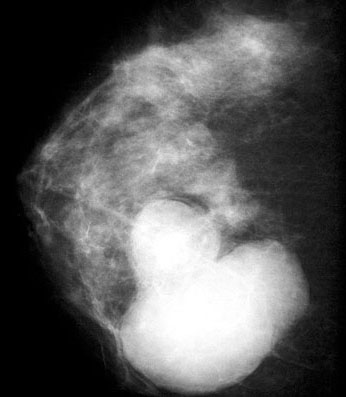

Radiology description

- Oval and lobulated lesions

- Hypoechoic on ultrasound

- Microcalcifications rare

Gross images